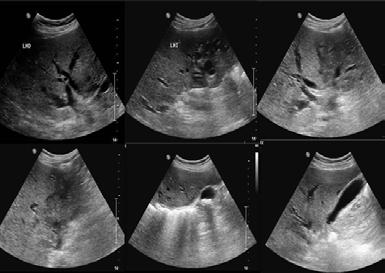

SONOGRAFÍA ABDOMINAL

Dra. Paola Pozo Rojas

P. 94